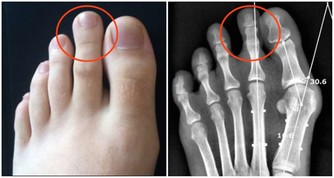

1、喝酒容易臉紅的人

研究表明,酒精在人體內的代謝要通過乙醛脫氧酶2(ALDH2)來完成,

人體內的乙醛脫氧酶2能將乙醛氧化為無致癌作用的乙酸,

最終分解成對人體無害的二氧化碳和水排出體外。

但當乙醛脫氧酶2正常基因發生變異之後,會使該酶失去活性,

從而導致飲酒後血中的乙醛濃度增高6倍多,

長期酗酒,體內的乙醛就會蓄積,最終可能導致肝癌發生。

專家發現,

乙醛脫氧酶2基因變異型攜帶者飲酒後往往會出現

臉紅、噁心和心動過速等神經系統症狀,所以飲酒後如果有上述症狀者,

應該提高警惕,戒酒或儘量減少酒精的攝入量,預防肝癌的發生。